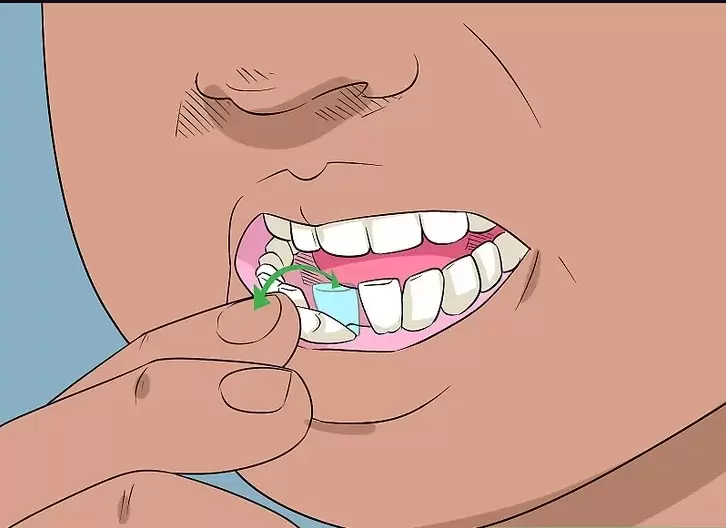

پیشگیری از این وضعیت با معاینات منظم دندانپزشکی و انجام رادیوگرافی از فک بالا در سنین رشد دندان عقل امکان پذیر است. همچنین رعایت بهداشت دهان و جلوگیری از ایجاد عفونت های لثه ای در اطراف دندان های عقبی نقش مهمی در سلامت سینوس دارد.

در صورتی که دندان عقل پتانسیل ایجاد فشار یا آسیب به سینوس را داشته باشد، متخصص ممکن است قبل از بروز عفونت، اقدام به کشیدن آن کند تا خطرات احتمالی به صفر برسد.